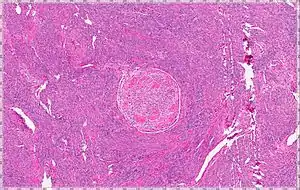

| Intravenous Leiomyoma |